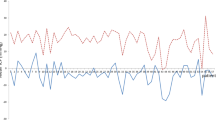

The difference of the absolute ICP values between sensor reservoir® and NEUROVENT®-P-tel probe showed a range of 0.0 and 14.5 mmHg. The mean value of the ICP difference was 4.2 mmHg with a standard deviation of 3.94 mmHg. The absolute ICP values from the sensor reservoir® and the NEUROVENT®-P-tel probe presented parallel alignment in nine cases. As representative example of parallel alignment of absolute ICP values measured via sensor reservoir® and the NEUROVENT®-P-tel probe in a selected patient is shown in Fig. 3. After three months the NEUROVENT®-P-tel probe was explanted and the measurement of ICP value via sensor reservoir® was continued for the follow-up examination (Fig. 3).

The Bland–Altman plot of collected data of 11 patients after three months shows all measurements within 95% confidence interval. Thus, there is no systematic difference between the two measuring techniques (Fig. 4). The mean difference is – 0.33 mmHg.

The Pearson correlation was significant in nine cases (Table 1). ICP values were normally distributed (Shapiro–Wilk-Test: NEUROVENT®-P-tel: W = 0.98555, p = 0.61045; sensor reservoir®: W = 0.98528, p = 0.05210) [11]. Each of data point is an average of the measured absolute ICP values, which were determined by two measurement procedures on 1 day and in one patient. Table 1 shows that in patient no. 1 a total of six parallel measurements of NEUROVENT®-P-tel and sensor reservoir® were performed in the period from day 1 after implantation of the sensor reservoir in secondary hydrocephalus until the last measurement before explantation of the NEUROVENT-P-tel (approved for max. 3 months) (see also Fig. 3). The absolute ICP values measured with the NEUROVENT®-P-tel probe were lower than the values measured with the sensor reservoir® in six cases (55%). Figure 3 shows the representative curve of the two measuring methods.

A telemetric measurement with both the NEUROVENT®-P-tel probe and the sensor reservoir® provided a comprehensible change in ICP values depending on the patient's body position (Fig. 5).

The measurement of ICP dynamics via NEUROVENT®-P-tel probe in relation to body position changes was successful in only three patients as they showed a good clinical outcome and were mobilizable. The ICP measurement via NEUROVENT®-P-tel probe shows similar dynamics of ICP change as the measurement via sensor reservoir® in VPS with a proGAV without gravitational valves (Fig. 5).